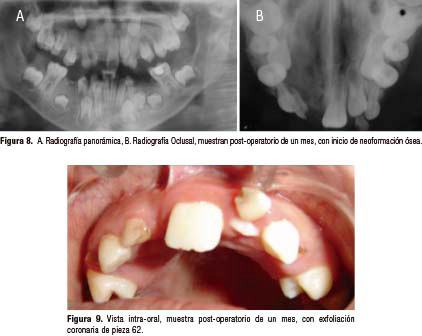

Durante la excisión quística se realizó la exodoncia de piezas comprometidas 11 y 12, posteriormente el paciente recibió tratamiento completo en diferentes áreas de acuerdo a planeamiento y posterior seguimiento clínico y radiográfico al primer mes, observándose inicio de neoformación ósea en región de lesión, mejor estado de conservación de piezas dentarias, pieza 62 en proceso de exfoliación coronaria (fig. 8 y 9). No consiguiendo controles posteriores por viaje de paciente al interior de la región.